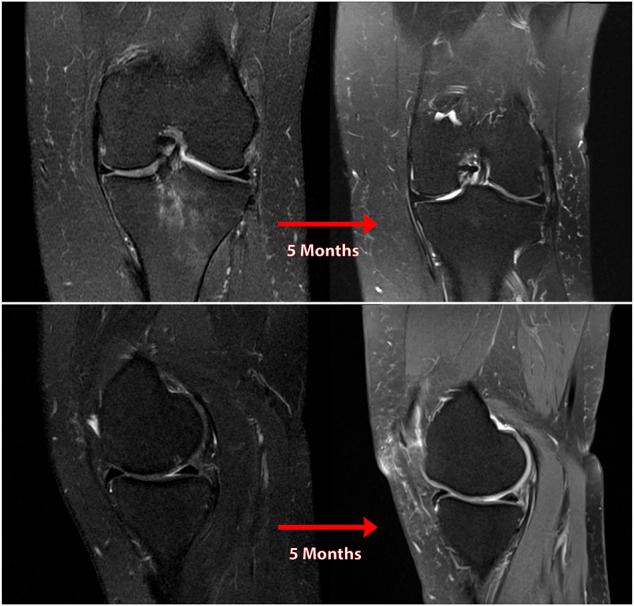

Posterior medial meniscus root tears (PMMRTs) make up a relatively notable proportion of all meniscus pathology and have been definitively linked to the progression of osteoarthritis (OA). While known risk factors for development of OA in the knee include abnormal tibial coronal alignment, obesity and female gender, PMMRTs have emerged in recent years as another significant driver of degenerative disease. These injuries lead to an increase in average contact pressure in the medial compartment, along with increases in peak contact pressure and a decrease in contact area relative to the intact state. Loss of the root attachment impairs the function of the entire meniscus and leads to meniscal extrusion, thus impairing the force-dissipating role of the meniscus. Anatomic meniscus root repairs with a transtibial pullout technique have been shown biomechanically to restore mean and peak contact pressures in the medial compartment. However, nonanatomic root repairs have been reported to be ineffective at restoring joint pressures back to normal. Meniscal extrusion is often a consequence of nonanatomic repair and is correlated with progression of OA. In this study, the authors will describe the biomechanical basis of the natural history of medial meniscal root tears and will support the biomechanical studies with a case series including patients that either underwent non-operative treatment (5 patients) or non-anatomic repair of their medial meniscal root tears (6 patients). Using measurements derived from axial MRI, the authors will detail the distance from native root attachment center of the non-anatomic tunnels and discuss the ongoing symptoms of those patients. Imaging and OA progression among patients who were treated nonoperatively before presentation to the authors will be discussed as well. The case series thus presented will illustrate the natural history of meniscal root tears, the consequences of non-anatomic repair, and the findings of symptomatic meniscal extrusion associated with a non-anatomic repair position of the meniscus.

后内侧半月板根部撕裂(PMMRTs)在所有半月板病变中占比较显著,并且已明确与骨关节炎(OA)的进展相关。虽然已知膝关节OA发展的风险因素包括胫骨冠状面排列异常、肥胖和女性性别,但近年来PMMRTs已成为退行性疾病的另一个重要驱动因素。这些损伤导致内侧间室平均接触压力增加,同时峰值接触压力增加,且相对于完整状态接触面积减小。根部附着的丧失会损害整个半月板的功能,并导致半月板挤出,从而损害半月板的力消散作用。经胫骨拉出技术进行的解剖学半月板根部修复在生物力学上已显示可恢复内侧间室的平均和峰值接触压力。然而,据报道非解剖学根部修复在将关节压力恢复到正常水平方面无效。半月板挤出通常是非解剖学修复的结果,并且与OA的进展相关。在本研究中,作者将描述内侧半月板根部撕裂自然病程的生物力学基础,并将通过一个病例系列来支持生物力学研究,该病例系列包括接受非手术治疗的患者(5例)或内侧半月板根部撕裂接受非解剖学修复的患者(6例)。作者将使用从轴向MRI得出的测量值,详细说明非解剖学隧道与天然根部附着中心的距离,并讨论这些患者的持续症状。还将讨论在向作者就诊之前接受非手术治疗的患者的影像学和OA进展情况。因此呈现的病例系列将说明半月板根部撕裂的自然病程、非解剖学修复的后果以及与半月板非解剖学修复位置相关的有症状半月板挤出的发现。